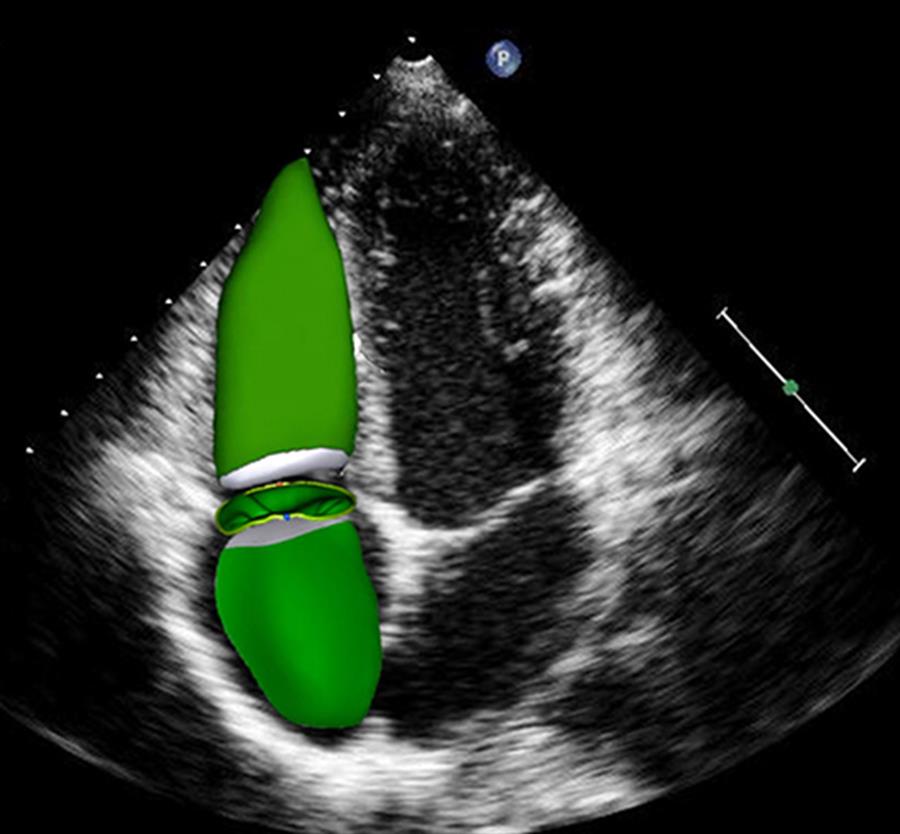

(Nella foto in alto: Esempio di ricostruzione eco-3D delle camere cardiache destre e dell’annulus tricuspidalico in un soggetto sano. I modelli 3D sono stati inseriti in una proiezione apicale 2D a 4 camere).

Diversi studi hanno evidenziato i vantaggi dell'ecocardiografia transtoracica tridimensionale (3D-TTE) per la valutazione dei volumi delle camere cardiache destre, e dell’anatomia e funzione della tricuspide. Per tale ragione, un recente studio del Monzino, – primo nome Gloria Tamborini, responsabile del Servizio Interventistica Strutturale dell’Area Imaging Cardiovascolare del Monzino, – si è proposto di valutare, con eco transtoracica 3D, atrio e ventricolo destri, nonché la

geometria e la funzione dell’annulus tricuspidalico, su pazienti da avviare a chirurgia della mitrale, con o senza concomitante annuloplastica della tricuspide, e su un gruppo di controlli sani.